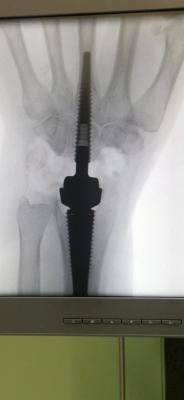

Pri posegu so uporabili večkomponentno protezo zapestja, ki je na trgu razmeroma nova, a se že izkazuje kot zelo učinkovita rešitev za bolnike z napredovalimi obrabnimi spremembami. Med operacijo kirurgi odstranijo poškodovane zapestne kosti, v dlančnici in koželjnici pripravijo natančno ležišče ter vanju vstavijo stabilno protezo. Ves kirurški poseg se sproti nadzoruje z rentgenskimi posnetki, kar zagotavlja visoko stopnjo natančnosti in varnosti. Operacija traja približno uro in pol, bolnik pa jo lahko opravi v regionalni ali splošni anesteziji.